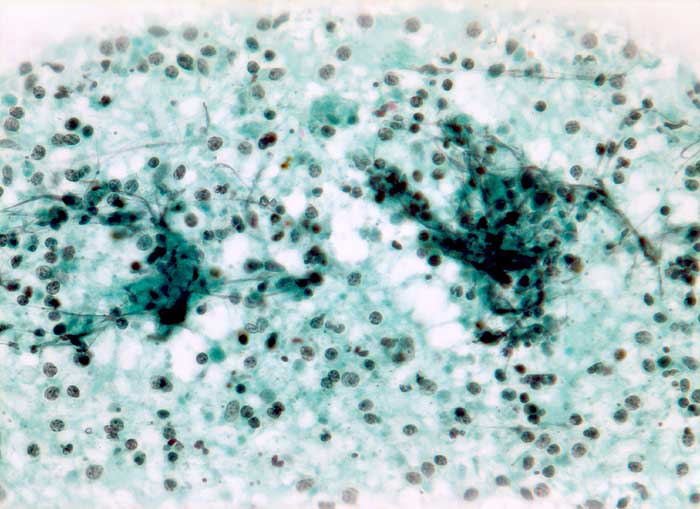

Die meist atrophischen Epitheloidzellen sind oft nur schwer von Venulenendothelien unterscheidbar und sind nur relativ selten zu deutlich erkennbaren Granulomen zusammengeballt. Bei Vorliegen von verkäsenden Granulomen erscheint der Ausstrich feinkörnig-detritisch. Eine granulozytäre Entzündung muss bei AIDS Patienten an eine Tuberkulose denken lassen.

Die Ziehl-Neelsen Färbung zum Nachweis der säurefesten Stäbchen kann nachträglich am Pap-gefärbten Präparat durchgeführt werden.